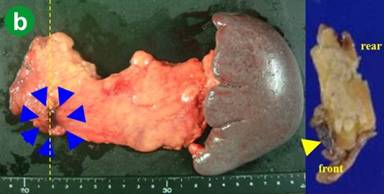

The patient was diagnosed with an intraductal papillary mucinous carcinoma with lymph-node metastasis, and underwent an operation. Laparotomy presented the cystic tumor and white-colored nodules on the surface of the transverse mesocolon (Figure 2a), which was histologically diagnosed as acinar cell carcinoma (Figure 3ab) and deemed unresectable.

Figure 3. Histological studies of the peritoneal nodules in the first operation (a. b.) and induration in the second operation (c. d.). |

In the second-look operation, there was no lesion that was deemed unresectable. The disseminations on the transverse mesocolon had disappeared, and the cystic main tumor had shrunk to the induration on the surface of the pancreas with a size of 8x4 mm. This lesion was excised and subjected to histological study, which demonstrated a small nest of cancer cells in the granulation tissue (Figure 3cd), which suggested a grade 2 effect of chemotherapy. Distal pancreatectomy was performed with lymph node dissection as well as ductal adenocarcinoma and resection of the transverse mesocolon (Figure 2b). There was no other microscopic finding except for remarkable infiltration of macrophages into the lymph node. Immunohistochemically, the tumor cells were positive for trypsin, lipase, and chymotrypsin, which are specific for acinar cell carcinoma.